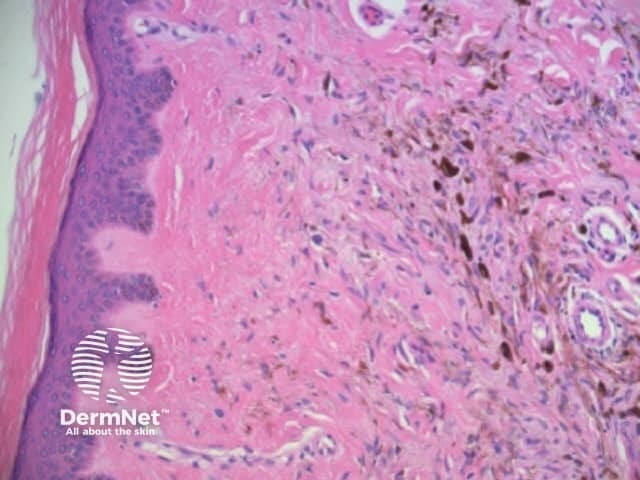

The combination of dermatoscopic structureless and reticular patterns may be due to marked pigmentation of lesional cells obscuring the pattern of lines and / or loss of the epidermal rete in part of the lesion. The former can be seen centrally in some dysplastic naevi, centrally or eccentrically in combined (true and blue) naevi and eccentrically in some melanomas. The latter may be seen with epidermal remodelling in melanoma (Figure 19a,b,c), past regression of melanocytic proliferations or due to an underlying expansile dermal lesion (Figures 20-22). The colour of the structureless zone depends on the level of the pigment within the skin: it may be white, if due to dermal fibrosis; skin coloured, if associated with epidermal remodelling in association with a proliferation of non-pigmented melanocytes; and black, brown, grey or blue, if due to heavy melanin pigmentation.

Figure 19a Figure 19b Figure 19c

Figure 20 Figure 21 Figure 22